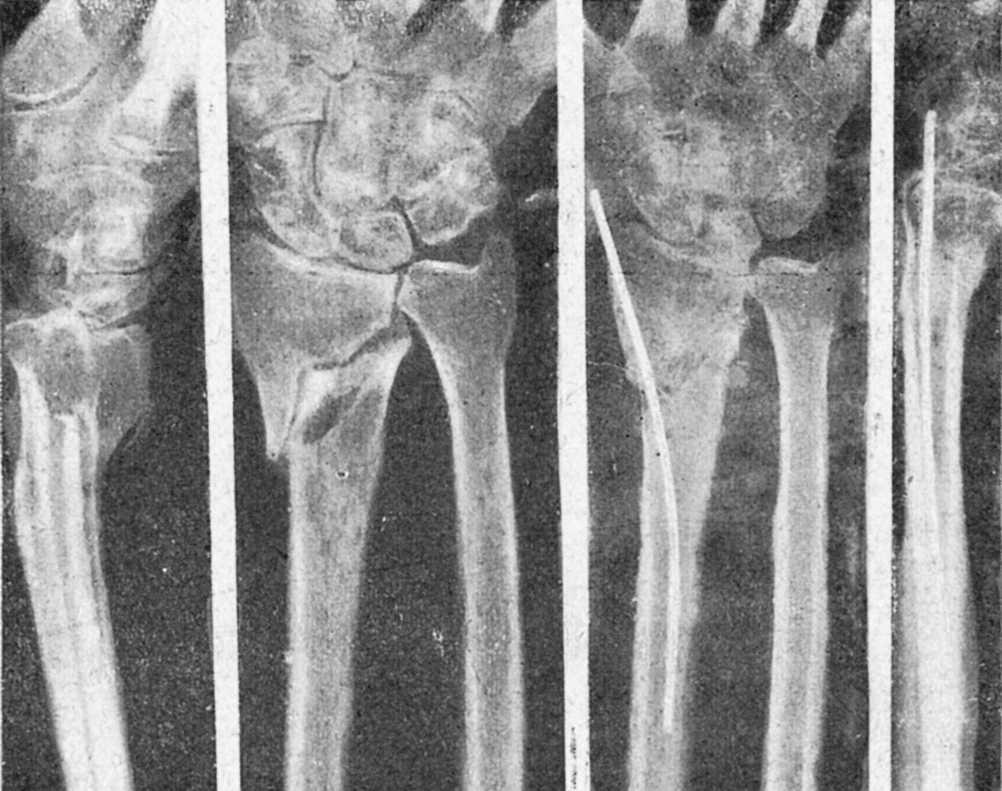

Figura 10. Pseudoartrosis cúbito y radio. La misma, con defectuoso enclavijamiento, tallo corto, poco presa en fragmento distal y diástasis; se complicó con infección postoperatoria y secuestro en anillo en foco radial, persistiendo posteriormente la pseudoartrosis del radio; único caso de infección que hemos tenido y que, sin propagación a canal medular, curó con la formación y extracción del secuestro.

Teniendo presente todo lo expuesto, y muy presente las ventajas de contención que presenta el procedimiento, comenzamos a usar, antes de disponer de tallos, alambres de Kirschner intramedulares en las fracturas de antebrazo, procedimiento con el que hemos obtenido buenos resultados y que continuamos utilizando, colocando alambres en ambos huesos o alambre en radio y tallo de Küntsche en el cúbito, sobre todo en fracturas bajas de este hueso, para evitar el «décalage», que el alambre no evita. Esta técnica con alambres la hemos extendido a casos atípicos en los que, introducido oblicuamente, su elasticidad le hace obrar de ballesta y permite mantener reducciones difíciles por otros procedimentos.